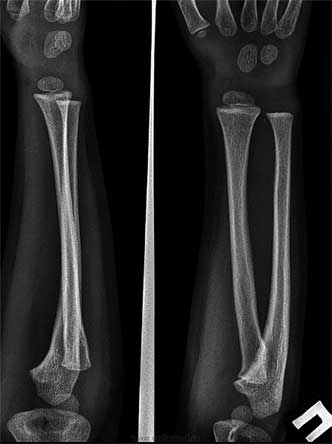

Очевидно, что немаловажную роль сыграл и случай с ребенком с диагнозом радиоульнарный синостоз. Это аномалия развития возникает в результате нарушения процесса внутриутробного развития малыша, когда нарушается процесс апоптоза – то есть процесс разделения лучевой и локтевой костей.

На иллюстрации справа пример синостоза сверху и нормы снизу:

Одним из пациентов на показательном сеансе Виолы Фрайман и был ребенок с этим диагнозом. Каково же было удивление врачей-ортопедов, когда примерно через 10 месяцев произошло сегментирование костей предплечья, и объем движения полностью восстановился! На последующие въедливые расспросы врачей Виола отвечала: «Я только освободила дорогу жизненным силам, а все остальное организм сделал сам».